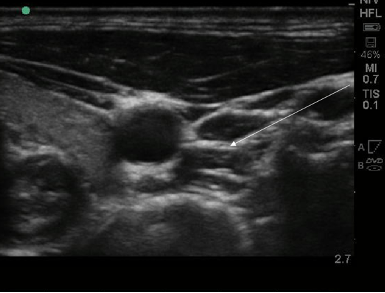

打针让王小姐摆脱失眠,这是一种什么神奇方法呢?专业术语为星状神经节阻滞,是疼痛科常用的一种微创治疗方法,常用于治疗头、颈、胸和上肢的疼痛性疾病。星状神经节位于颈部第7椎体横突表面,是人体交感神经链中非常重要的组成部分。星状神经节阻滞可降低交感神经兴奋造成的植物神经功能紊乱,调节松果体对褪黑素的分泌和生物节律性,从而延长睡眠时间、改善睡眠质量。在超声引导下将局部麻醉药精准地注射在含星状神经节的疏松结缔组织内,是一种创伤小、安全性高的治疗失眠的绿色方法。(见下图)